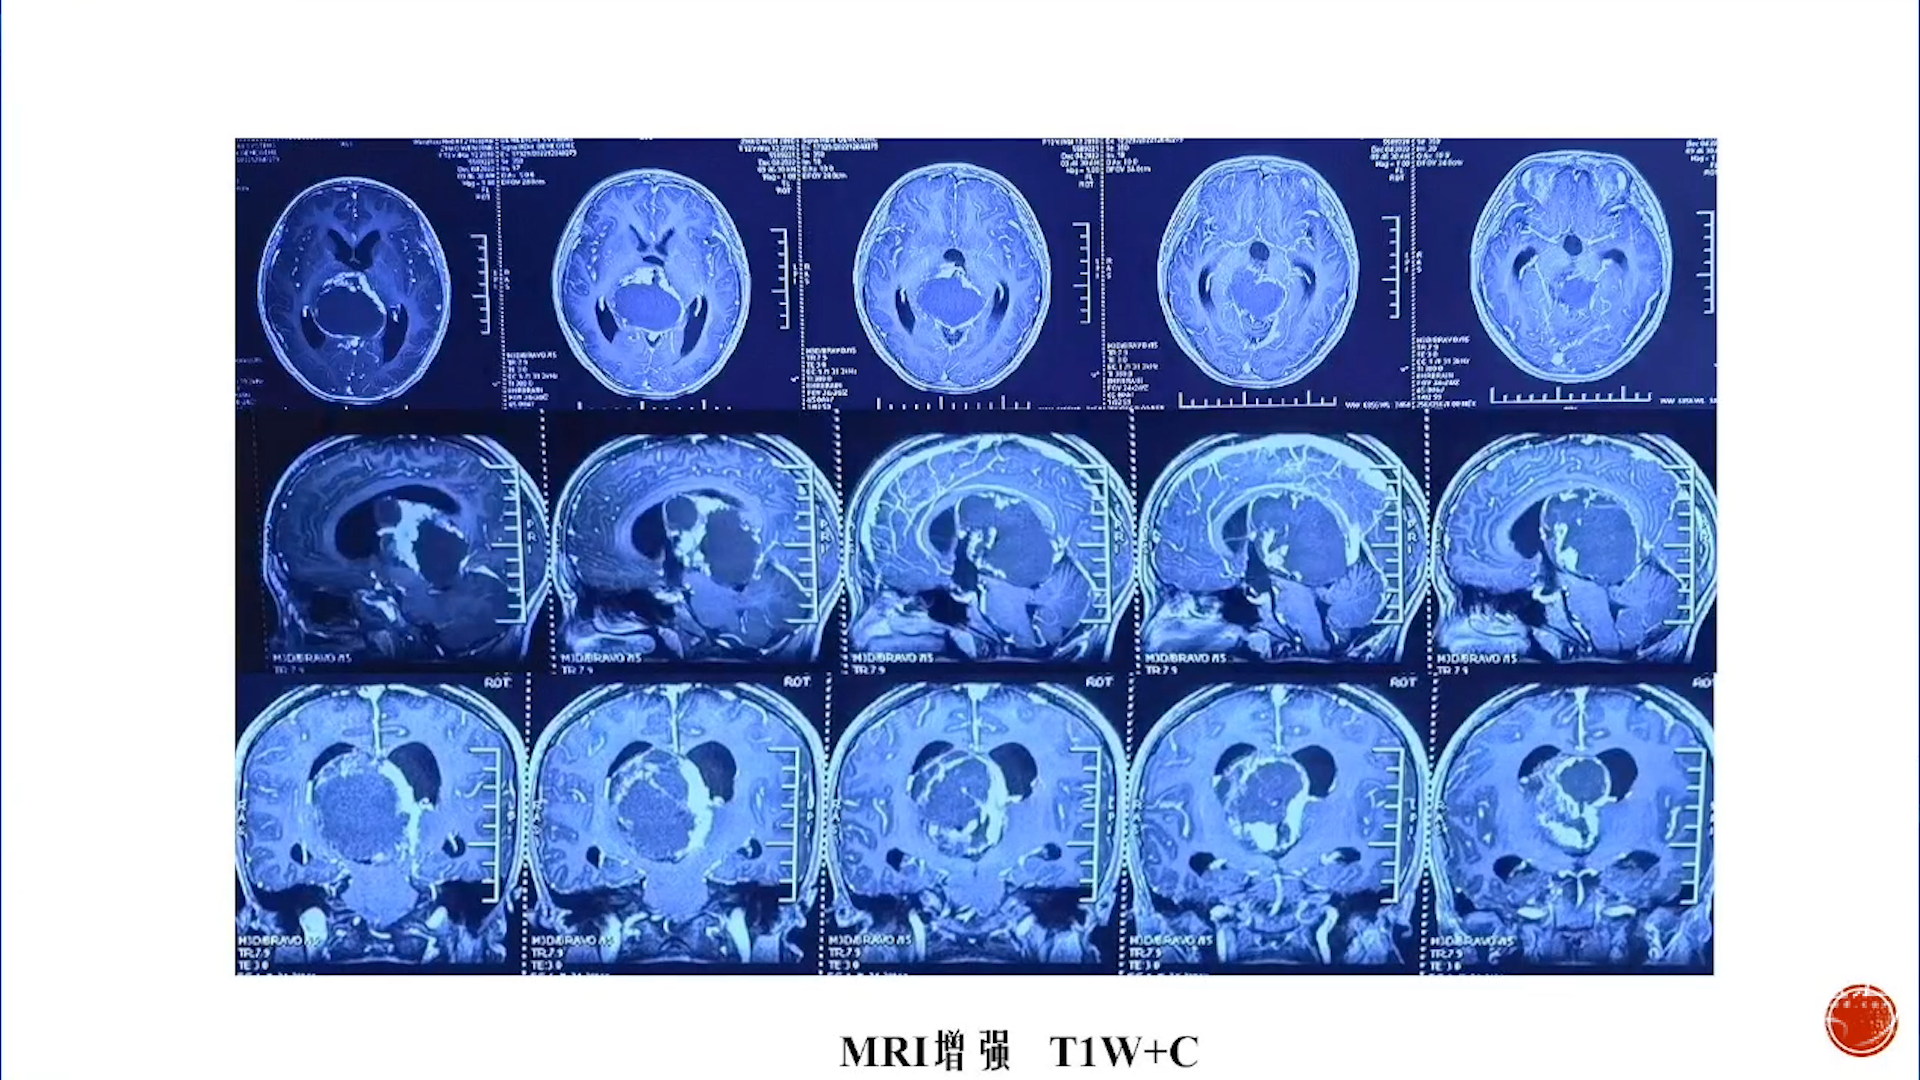

小脑星形细胞肿瘤